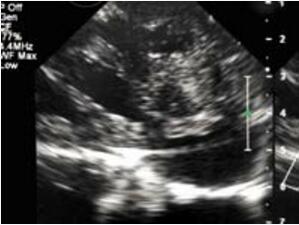

笔者第一次遇到这种情况是在进行肌部室间隔缺损封堵时,传统的胸骨切口并不是封堵某些缺损的最佳入路。当然,可能通过旋转拖拉可以把心脏通过切口暴露出来,但是切口越小孩子越大越难操作。而且植入封堵器的直行方向会消失,从而导致封堵器超声图像形态变形。经食管超声心动图图像在心尖部卷曲的情况下也会变得复杂。对于这些病人,笔者设计了一种非常简单而且比标准方法更美观的手术,特别适用于极度靠近心脏前部几乎没有间隔边缘的心尖部缺损患者。患者向右旋转20~30度(图10-44),心脏上缘的探查借助经胸超声心动图进行,由第4 肋间入路(图10-45),此方法可以无需任何牵引精确到达心脏上部和室间沟,清晰的暴露穿刺位置。而且可以按照标准方法直接关闭任何心尖部缺损(图10-46,图10-47)。笔者提供的病例中有一个10月龄、10kg的患儿。选用 SQFDQ 9mm 封堵器封闭7mm的心尖部室间隔缺损。

改进也针对复杂解剖的心尖部缺损,笔者称之为“逆向封堵”。虽然病例罕见但是有时会有伴有巨大心尖部壶腹需要较大封堵器方能完成的病例。有时候很值得怀疑这种病人是否能够局部封闭。存在一个缺损隧道,右室肌小梁部存在射流束。隧道方向与右房-右室轴线平行,垂直于右室前壁到缺损之间的轴线,因此根据笔者们的经验穿刺右室前壁通过经典方法穿过缺损极难(图10-48)。如果不改变导丝方向或者在心脏扭曲角度下穿刺前壁将无法通过此类缺损,而且该部位的肌小梁结构可能会不断缠绕导丝,此时由于输送系统是有弹性的,封堵也会受阻。如果遇到此类患者可以通过右房途径进行,切口可在右侧肋间进行。笔者利用一个更简单有效的方式进行。心脏上部拖出切口而不破坏TEE图像暴露室间沟(缺损壶腹部所在),延右室轴线直接穿刺进入通过缺损(图10-49)。而且隧道封堵的完成按照标准方式进行(图10-50)。在提供的病例中笔者选用了一个SQFDQ-Ⅰ14mm的封堵器,封闭了一个2岁患儿 的缺损。值得一提的是,笔者的病人没有任何并发症,没有左室出血危险。在笔者印象中患儿年龄也不比其他方法完成的患者年龄大。